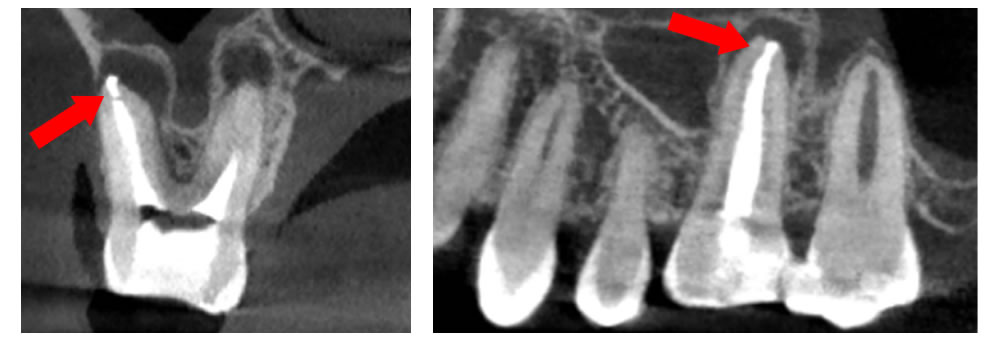

CTでの根管精密検査

根管内は非常に複雑な形状をしているため、レントゲンだけでは、全てを把握する事が出来ません。特に、歯根の先端に膿が溜まる病変などはレントゲンに写らない事も多く、歯の痛みや違和感を感じながらも、どこに原因があるのか分からないと言う状況になる事も少なくありません。

根管内は非常に複雑な形状をしているため、レントゲンだけでは、全てを把握する事が出来ません。特に、歯根の先端に膿が溜まる病変などはレントゲンに写らない事も多く、歯の痛みや違和感を感じながらも、どこに原因があるのか分からないと言う状況になる事も少なくありません。

そのため当院では、歯科用CTでの3次元精密検査を実施しています。レントゲンでは写らない病巣の発見や、見落としがちな根管の把握が出来るため、原因の早期発見、悪化防止が適切に行えます。

▲他の歯科医院での根の治療

▲当院でやり直した治療

他の医院で根の治療を行った患者様が「痛みを感じる」と来院された例があります。診察すると、治療を受けた部分は歯の先端まで白い充填物が入っておらず隙間だらけで、先端に膿が溜まっていました。そこで当院は根の先端まで隙間なく白い充填物を入れて痛みを消失させました。ここで可能であれば、歯を長期使用するためにしっかりした被せ物をします。被せ物は充填物同様、その歯の予後を左右する大事な要因となります。

空洞に挟まったハリを除去することが可能

過去に他の医院で治療した際の折れたハリ(赤丸)が入っているレントゲン。

ハリを除去し、徹底的に洗浄したレントゲン。

空洞を根の先までしっかり埋めたレントゲン。

根の治療はハリを使用するため、ハリが折れて空洞の中に挟まってしまうケースがあります。これは治療の特性上、どうしても起こりうることなのですが、隙間を埋めることができずに空洞があると、しっかり洗浄されていないため、そこが痛み始めたらどうすることもできません。しかし、当院ではその根の中の細かい空洞に挟まったハリを除去し、治療することが可能です。ある患者様が半年以上もジンジンする痛みに悩まされ、いくつかの医院に行かれたそうですが治せる医院がなく、諦めかけていたそうです。しかし、当院にお越しいただいてハリを除去し治療を行ったところ、3回の通院のみで痛みを完全になくすことができました。

【術後のCT画像】